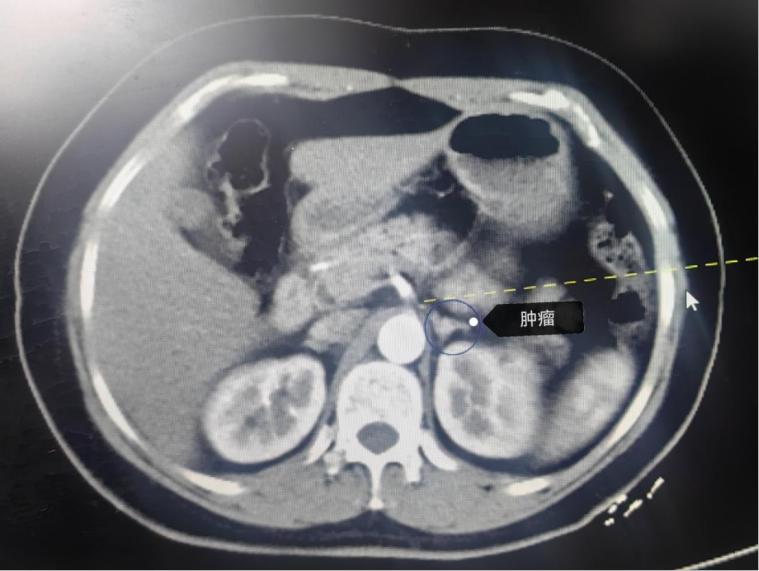

今年2月27日,罗女士因高血压来到安医门诊就诊。不同于普通高血压患者,年仅38岁的她,即便按时服用降压药,血压依旧居高不下。凭借丰富的临床经验,心血管内科医生敏锐地察觉到:这很可能不是普通的原发性高血压,背后或许另有隐情!随后,罗女士被收入心血管内科住院。一系列详细检查后,真相逐渐浮出水面——她被确诊为“原发性醛固酮增多症”,CT检查更是发现左侧肾上腺占位!这意味着,罗女士的高血压极有可能是肾上腺疾病引发的继发性高血压!多学科协作抽丝剥茧,精准锁定“罪魁祸首”

为明确病灶,医生团队决定采用介入AVS(经皮肾上腺静脉采血)术进行精准定位。这项技术能通过采集肾上腺静脉血,准确判断哪一侧肾上腺才是导致激素异常分泌的“真凶”。经过严谨细致的检查,左侧肾上腺被最终锁定,且具备外科手术指征!